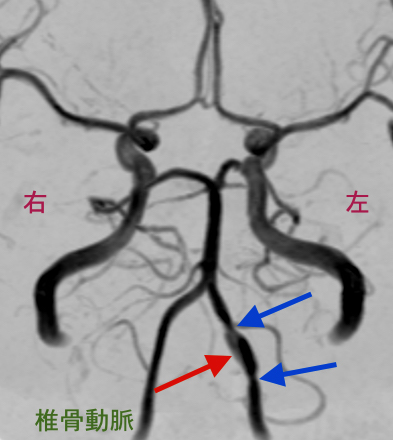

MRA検査(MRIを使って脳血管を描き出す方法)で脳血管の変化をとらえる事で、可逆性脳血管攣縮症候群(RCVS)や椎骨動脈解離といった重大な疾患が見つかる事があります。

MRA検査を見たところ、

右椎骨動脈(右の首から後頭部へ行く血管)が変形しています。この所見だけを見ると、可逆性脳血管攣縮症候群とも椎骨動脈解離とも取れます。